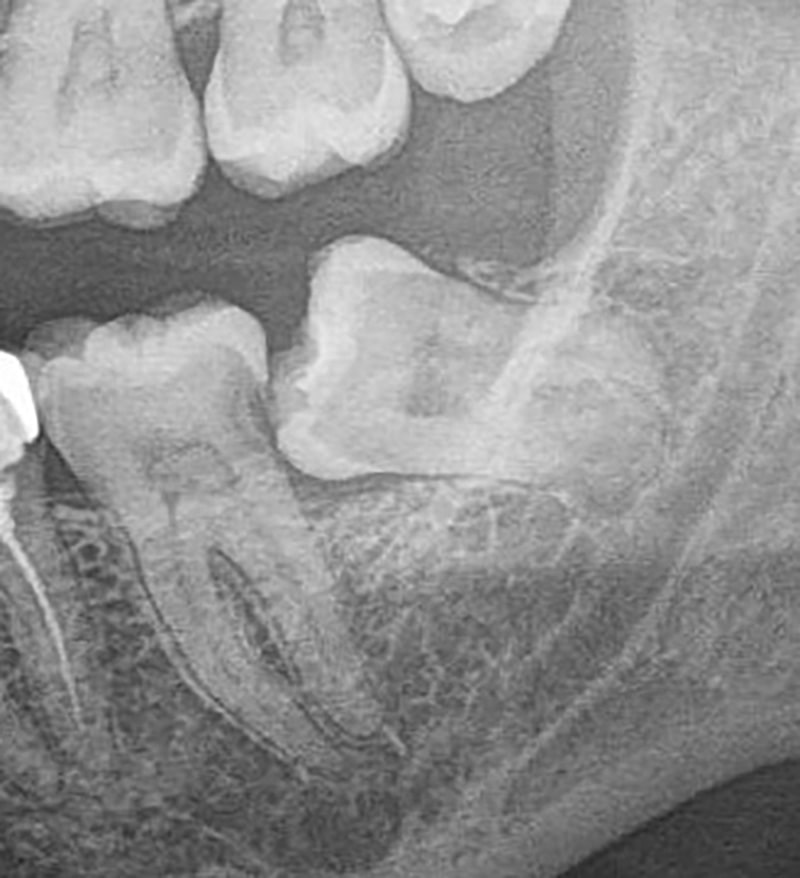

Before extraction, we evaluate your oral health using digital X-rays or CBCT scans to assess root structure and bone support.